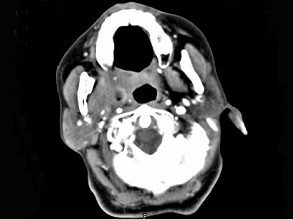

女,52岁,咽喉部疼痛半个月,伴低热,CT如图所示,可能诊断为()

A.咽旁脓肿

B.咽部神经鞘瘤

C.鼻咽血管纤维瘤

D.咽旁淋巴瘤

E.咽旁转移癌

[单选题]女,52岁,咽喉部疼痛半个月,伴低热,CT如图所示,最可能的诊断是()A.咽旁脓肿B.咽部神经鞘瘤C.鼻咽纤维血管瘤D.咽旁淋巴瘤E.咽旁转移瘤

[单选题,A2型题,A1/A2型题] 女,52岁,咽喉部疼痛半个月,伴低热,CT如图所示,可能诊断为()。A . 咽旁脓肿B . 咽部神经鞘瘤C . 鼻咽血管纤维瘤D . 咽旁淋巴瘤E . 咽旁转移癌

[单选题]女,52岁,咽喉部疼痛半个月,伴低热,CT如图所示,可能诊断为()A .咽旁脓肿B .咽部神经鞘瘤C .鼻咽血管纤维瘤D .咽旁淋巴瘤E .咽旁转移癌

[单选题]女,52岁,咽喉部疼痛半个月,伴低热,CT如图所示,可能诊断为()A . 咽旁脓肿B . 咽部神经鞘瘤C . 鼻咽血管纤维瘤D . 咽旁淋巴瘤E . 咽旁转移癌

[单选题]女,52岁,咽喉部疼痛半个月,伴低热,CT如图所示,最可能的诊断是()A . 咽旁脓肿B . 咽部神经鞘瘤C . 鼻咽纤维血管瘤D . 咽旁淋巴瘤E . 咽旁转移瘤